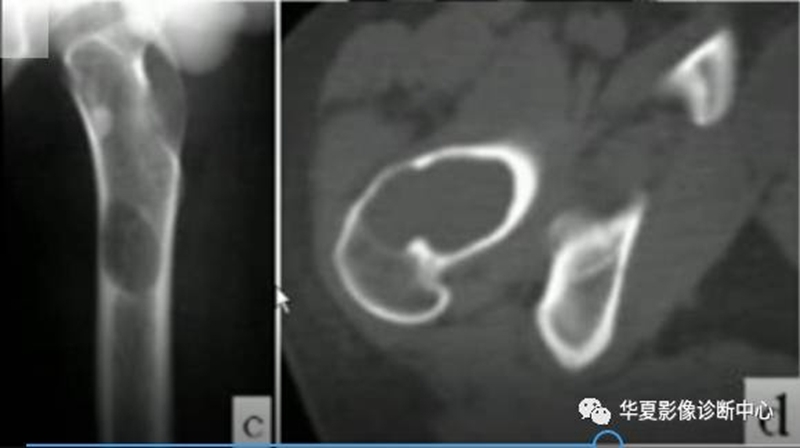

囊状破坏,膨胀性破坏,溶骨性破坏。

左股骨上段囊状骨破坏区,边缘光滑,无硬化边